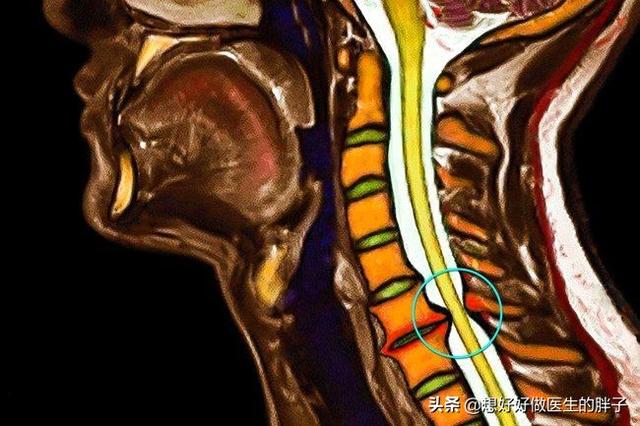

Wenn die Halswirbelsäule einen Tastaturbruch oder Osteophyten aufweist, die zur Bildung von Knochenmark führen und denSchulterschmerzen treten auf, wenn die Nervenwurzel nicht an ihrem Platz ist. Diese Schmerzen sind meist stechend, wie ein elektrischer Schlag, und stehen im Allgemeinen nicht in Zusammenhang mit der Bewegung der Schulter.Das heißt, dass dieser Schmerz unabhängig vom Winkel der Schulterbewegung auftritt. Stattdessen kann es einen Zusammenhang zwischen diesen Schmerzen und der Aktivität der Halswirbelsäule geben, z. B. kann eine übermäßige Neigung der Halswirbelsäule nach hinten oder ein Vorbeugen des Kopfes nach vorne die Nervenwurzeln reizen und die Schmerzen verschlimmern.

Einfach ausgedrückt: Der Schmerz manifestiert sich in der Schulter, aber das Problem liegt in der Halswirbelsäule!

Wenn der Verdacht besteht, dass die Halswirbelsäule die Ursache der Schulterschmerzen ist, muss eine Untersuchung durchgeführt werdenMRT der HalswirbelsäuleIm Folgenden sind einige Beispiele aufgeführt, wie man sicherstellen kann, dass ein zervikaler Bandscheibenvorfall oder eine Anomalie in der knöchernen Struktur eine Nerveneinklemmung verursacht, und wenn dies mit einer Schwäche der Schultern oder der oberen Gliedmaßen einhergeht, kann es sogar notwendig sein, eineElektromyographieDie Untersuchung klärt, ob die Nerven geschädigt sind. BehandlungsmöglichkeitenAkupunktur und Moxibustion durchführen oder durchführen lassenNachfolgend sind einige der wichtigsten Fragen aufgeführt, die im Hinblick auf die Erreichung einer angemessenen(einen Wagen) ziehenWenn die Schmerzen stark sind, können SieOrale schmerzstillende und entzündungshemmende MedikamenteDa die meisten dieser Schmerzen auf ein Ödem an den Nervenwurzeln zurückzuführen sind, ist es möglich, einige oral einzunehmen.Medikamente gegen Ödeme,Sie können auch einige Physiotherapie wie transkutane elektrische Nervenstimulation, und in der Regel gibt es Erleichterung nach systematischer Behandlung. Diese Zeitspanne kann in der akuten Phase 1~2 Wochen dauern, und es wird etwa drei Monate dauern, bis sich die Beschwerden langsam bessern.Die Patienten müssen darauf vorbereitet sein und dürfen nichts überstürzen, denn bei dieser Art von Problemen muss man alles langsam angehen.。